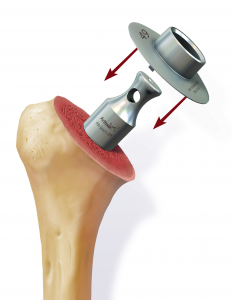

Daraufhin wird der Kalottenträger mittels der selbstschneidenden Hohlschraube im Oberarmschaft befestigt. Nun wird der endgültige Prothesenkopf angebracht (Abb. 49).

In diesem Fall kann das Gelenk durch ein sog. inverses Prothesen-System nach Prof. Paul Grammont ersetzt werden. Hierbei wird eine „Halbkugel“ (Glenosphäre) auf die ursprüngliche Pfanne aufgeschraubt und eine konvex geformte „Humeruspfanne“ im Oberarmknochen fixiert (Abb. 48). Der Oberarm wird dadurch wieder nach „unten“ verlagert und die Funktion des M. deltoideus wird verbessert (Abb. 49).